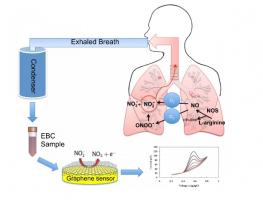

Actualité publiée le 28/07/2017ASTHME : Bientôt un tracker de crise ?